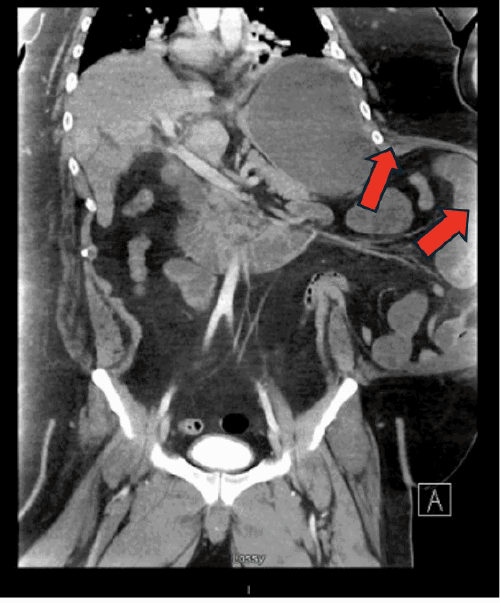

The patient was initially managed conservatively with bowel rest, intravenous hydration, and electrolyte repletion, targeting standard resuscitation parameters (mean arterial pressure >65 mmHg, heart rate <120 bpm, urine output ≥0.5 mL/kg/hr, capillary refill <2 seconds, and normalization of BUN, creatinine, electrolytes, and lactate). A nasogastric tube was placed for decompression, and intravenous analgesia was administered judiciously, avoiding narcotics where possible. Serial laboratory evaluations and physical examinations were performed to monitor for signs of worsening systemic inflammatory response, metabolic acidosis, increasing abdominal distension, or the development of peritonitis. Despite these measures, on hospital day five, the patient experienced a significant clinical deterioration, manifesting as sepsis and acute respiratory failure. A repeat CT scan at this time demonstrated a new, large, loculated, mixed-density pleural effusion on the left side (Figure 2). Crucially, this scan provided complete visualization of the hernia sac, revealing a persistent small bowel obstruction and a new extraperitoneal fluid collection within the abdominal wall, which appeared to be tracking superiorly into the pleural cavity (Figure 3).

Figure 3. CT Demonstrating Extraperitoneal Bowel Perforation and Pleuro-Abdominal Communication. Published with Permission

Image shows extraperitoneal collection of fluid and gas within the left abdominal wall (arrow), consistent with bowel perforation within the hernia sac. Note the evidence of contrast extravasation and a communicating tract (arrow) extending from this collection superiorly towards the left pleural cavity

Given these findings, the patient was taken emergently to the operating room. A left-sided Wayne pigtail catheter was initially placed into the pleural space for decompression, yielding an immediate return of approximately 3,000 mL of succus entericus (Figure 4A), confirming a pleural effusion entericus. Correct intrapleural placement of the catheter was verified. Subsequently, the hernia sac was explored via a left flank incision. This revealed a 5 cm rupture of the hernia sac containing a strangulated and perforated loop of small bowel. Enteric contents were observed draining from this perforation into the abdominal wall planes and tracking superiorly through fascial defects into the pleural space (Figure 4B). The necrotic segment of small bowel was resected, and intestinal continuity was restored with a stapled anastomosis; the repaired bowel was then returned to the peritoneal cavity. A diagnostic laparoscopy was performed, which confirmed the absence of any primary diaphragmatic defect, further intraperitoneal bowel ischemia, or gross peritoneal contamination. Further exploration of the abdominal wall revealed that the chronic, large left flank hernia had significantly distorted the normal anatomical planes, including the fascial and muscular connections with the diaphragm and chest wall. This distorted anatomy likely facilitated the upward tracking of the succus entericus from the extraperitoneal perforation along the path of least resistance into the pleural space, as depicted on the CT images (Figure 3). This abnormal abdominal wall-to-pleural communication was also visualized thoracoscopically using a 30-degree scope.